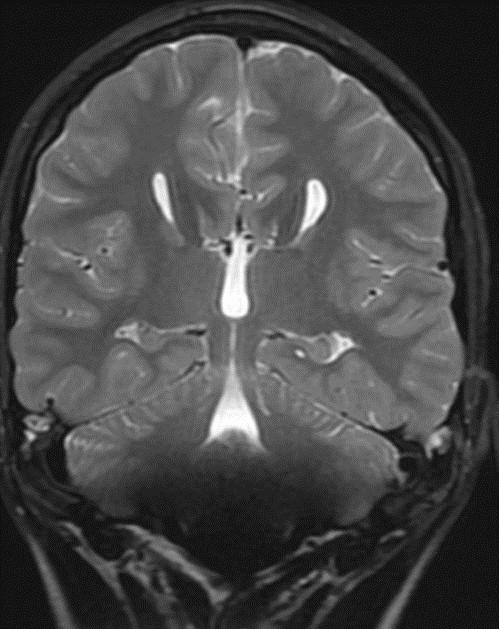

Sweep the Midline: What parts are missing?

Run the Rim…where is the cortex “too thick?”

“Missing”=disorganized rostrum, genu, anterior body of the corpus callosum Cortex of the anterior medial frontal lobes “too thick” with fused grey matter across the anterior midline where the “genu” should be.